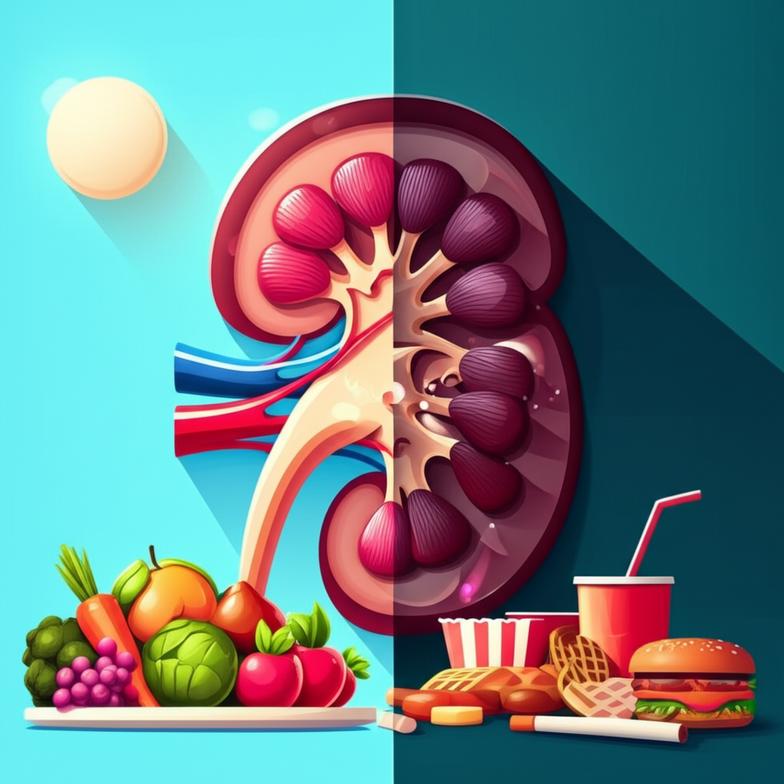

ปัจจัยเร่งการเสื่อมของไต: โภชนาการและพฤติกรรมในชีวิตประจำวัน

ภาวะไตเสื่อมมักเป็นผลรวมจากการสะสมของปัจจัยเสี่ยงหลายประการที่เกี่ยวข้องกับวิถีชีวิตและโภชนาการ การเข้าใจปัจจัยเหล่านี้เป็นก้าวสำคัญในการ ชะลอการเสื่อมของไต และปรับเปลี่ยนพฤติกรรมเพื่อสุขภาพที่ดีขึ้น ปัจจัยเสี่ยงที่พบบ่อยได้แก่:

- การบริโภคอาหารที่ไม่เหมาะสม: การรับประทานอาหารที่มีโซเดียมสูง น้ำตาลสูง ไขมันทรานส์ และเนื้อสัตว์แปรรูปมากเกินไป อาจเพิ่มภาระการทำงานของไตและนำไปสู่การอักเสบเรื้อรัง

แนวทางเวชศาสตร์ชะลอวัยเน้นการใช้สารอาหารและโภชนาการที่เหมาะสมเพื่อฟื้นฟูการทำงานของไตและลดภาระการทำงานของอวัยวะนี้ การเลือกรับประทานอาหารที่ถูกต้องถือเป็นยาขนานเอกที่สำคัญที่สุดในการดูแลไต:

- เน้นอาหารธรรมชาติและโฮลฟู้ด: เพิ่มสัดส่วนผัก ผลไม้ ธัญพืชไม่ขัดสี และโปรตีนคุณภาพดีจากพืชหรือปลา ลดอาหารแปรรูปและอาหารที่มีสารปรุงแต่ง

- จำกัดโซเดียมและน้ำตาล: ลดการเติมเกลือและหลีกเลี่ยงอาหารรสจัด รวมถึงเครื่องดื่มและอาหารที่มีน้ำตาลสูง ซึ่งเป็นสาเหตุหลักของโรคความดันโลหิตสูงและเบาหวาน